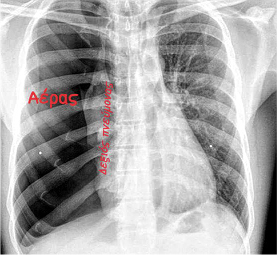

Η διάγνωση τίθεται κατά την κλινική εξέταση. Όπως είπαμε ο πνεύμονας δεν μπορεί να εκπτυχθεί και στην ακρόαση πνευμόνων το αναπνευστικό ψιθύρισμα είναι πολύ μειωμένο ή απουσιάζει.

Η ακτινογραφία θώρακας θέτει τη διάγνωση. Ίσως να χρειαστεί να γίνει και αξονική τομογραφία θώρακος.

Εκεί διενεργήθηκε ακτινογραφία θώρακος όπου τέθηκε η διάγνωση αυτόματος πνευμοθώρακας.